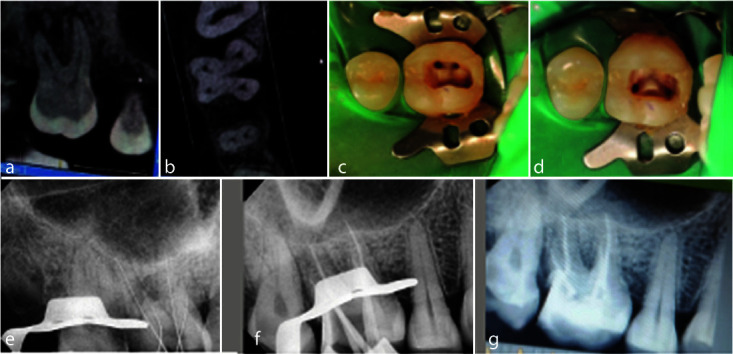

An in-depth understanding of the anatomical variations of maxillary molars is essential for endodontic success. Unlike the maxillary second molars, the presence of a second palatal root is uncommon in the first maxillary molar. This case report describes two cases of non-surgical management of maxillary molars with extra palatal roots. Careful clinical examination, knowledge of the internal anatomy, and the use of advanced radiographic modalities like cone beam computed tomography (CBCT) can reveal the presence of variations in the internal and external anatomy of any tooth. Therefore, for nonsurgical as well as surgical management clinicians should always watch out for any deviations in a tooth and utilize all the available tools to diagnose and manage them successfully.